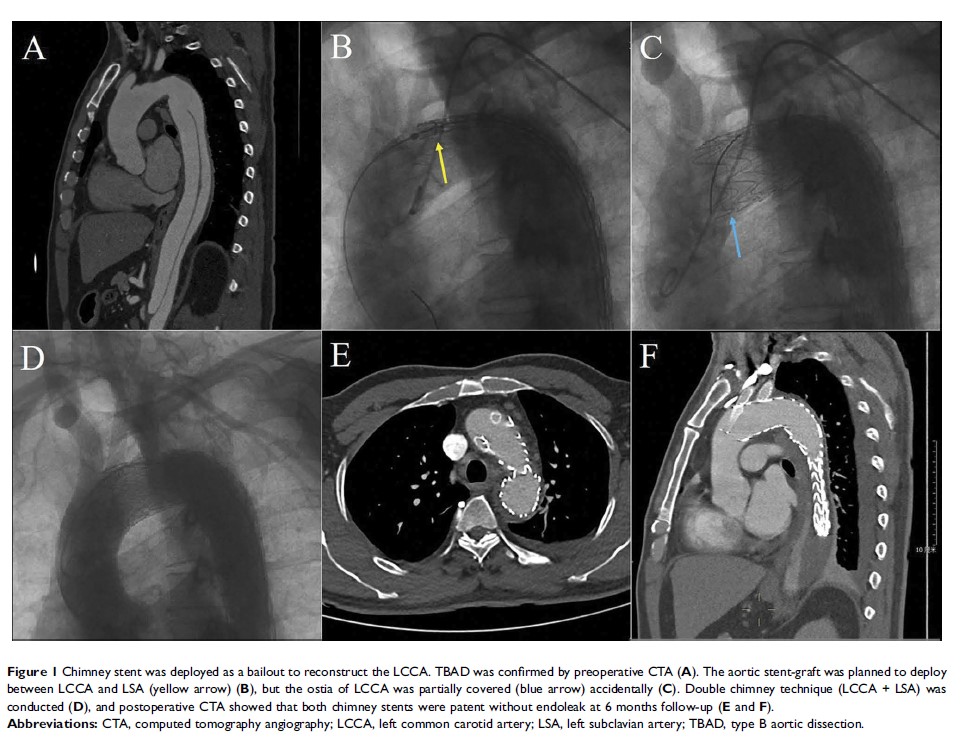

烟囱技术治疗主动脉弓部疾病的疗效:226 例单中心经验